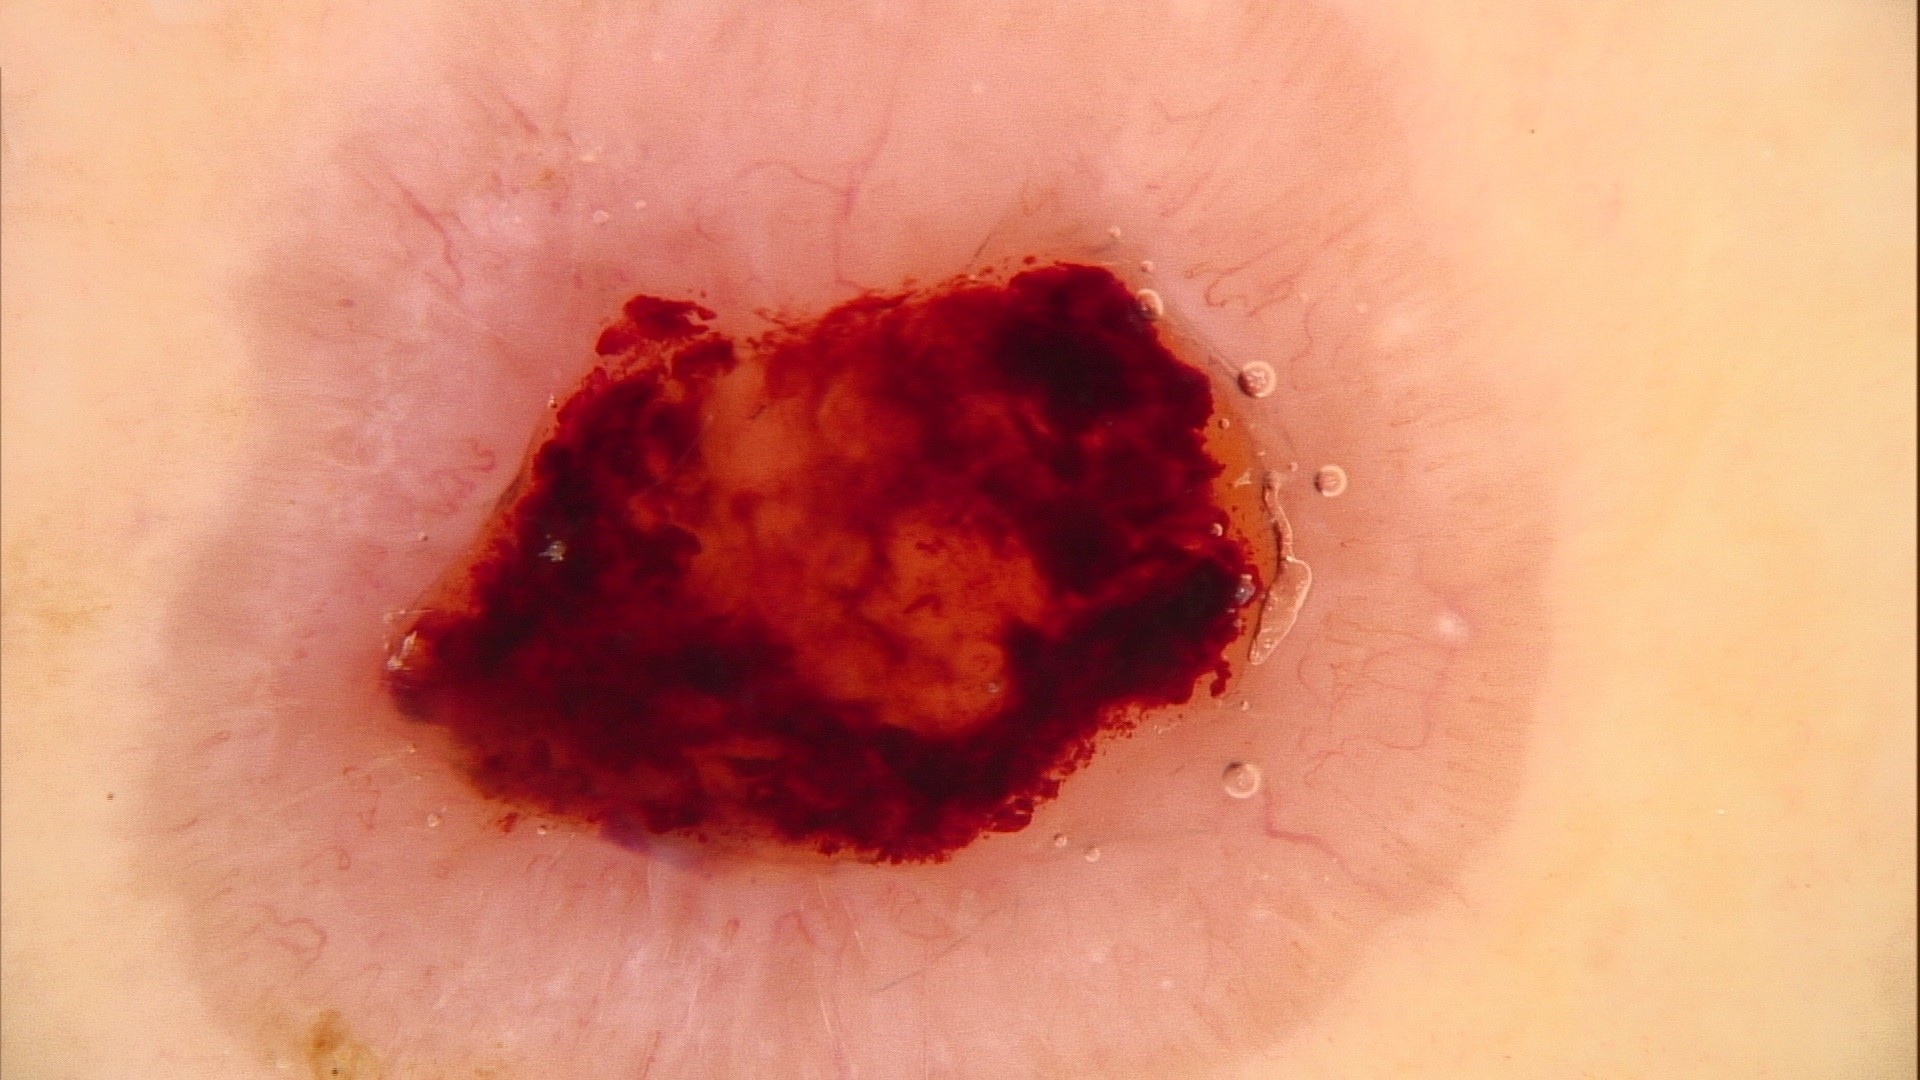

Clinical features

- Nodular variant usually presents as a pearly pink or flesh colored papule or nodule with arborizing and branching vessels (Br J Dermatol 2002;147:41)

- In the past, ulceration of a nodular BCC gave rise to the term rodent ulcer

- Tumor with ulceration has characteristic rolled borders

- Superficial variant presents with scaly macules, patches or plaques with an erythematous surface

Clinical images